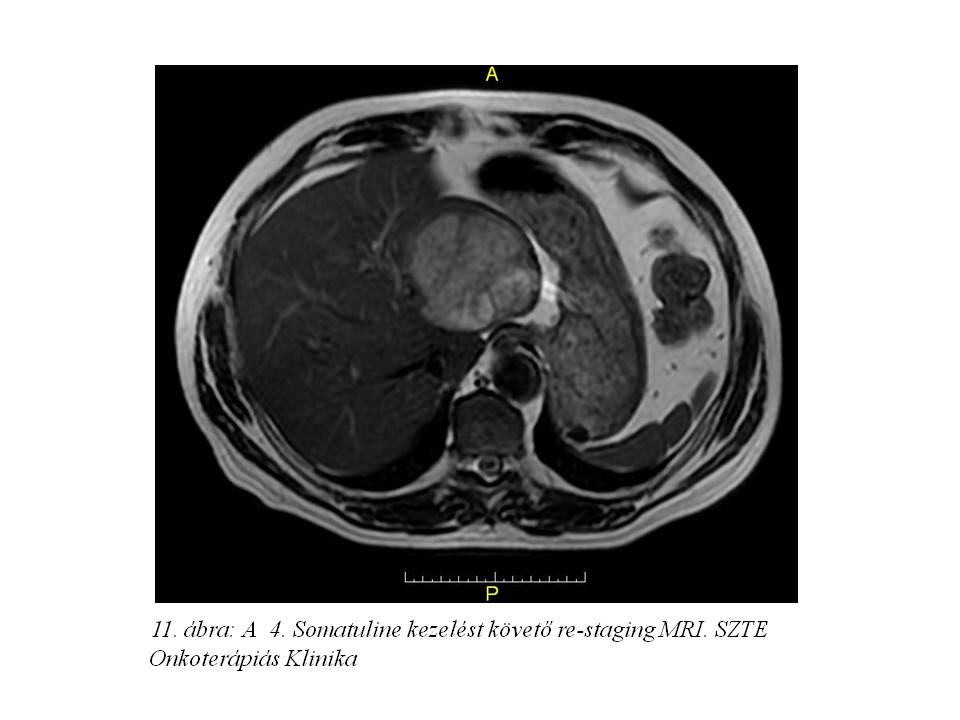

Ezt követően bőrgyógyászati ellátás vált szükségessé testszerte jelentkező viszkető urticaria miatt, felmerült octreotidra való túlérzékenység lehetősége. Emiatt kezelését a továbbiakban lanreotiddal (Somatuline) folytattuk, ugyancsak 4 ciklusonként végzett re-staging mellett. Jelenleg a hasi MR vizsgálaton (11. ábra, 12. ábra, 13. ábra) változatlan status látható, a chromogranin szint emelkedése mellett (266,9 – 310 – 427 ng/ml).